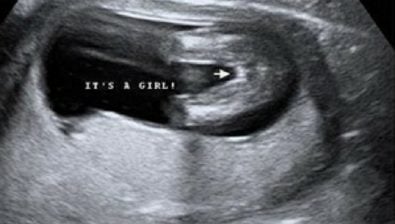

Ultrasound at 34 Weeks